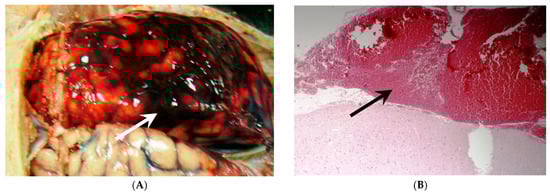

- Crompton, M.R. Hypothalamic lesions following the rupture of cerebral berry aneurysms. Brain 1963, 86, 301–314. [Google Scholar] [CrossRef]

- Hayman, E.G.; Wessell, A.; Gerzanich, V.; Sheth, K.N.; Simard, J.M. Mechanisms of Global Cerebral Edema Formation in Aneurysmal Subarachnoid Hemorrhage. Neurocritical Care 2017, 26, 301–310. [Google Scholar] [CrossRef]